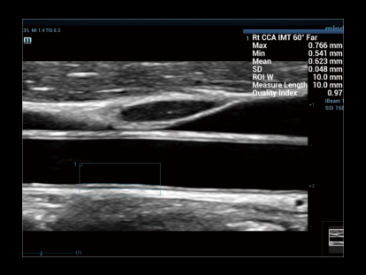

EvaluaciĂłn inteligente de la esteatosis hepĂĄtica mediante el cĂĄlculo automĂĄtico del brillo del hĂgado con la corteza renal en modo B.

CompensaciĂłn de respiraciĂłn

CompensaciĂłn de respiraciĂłn